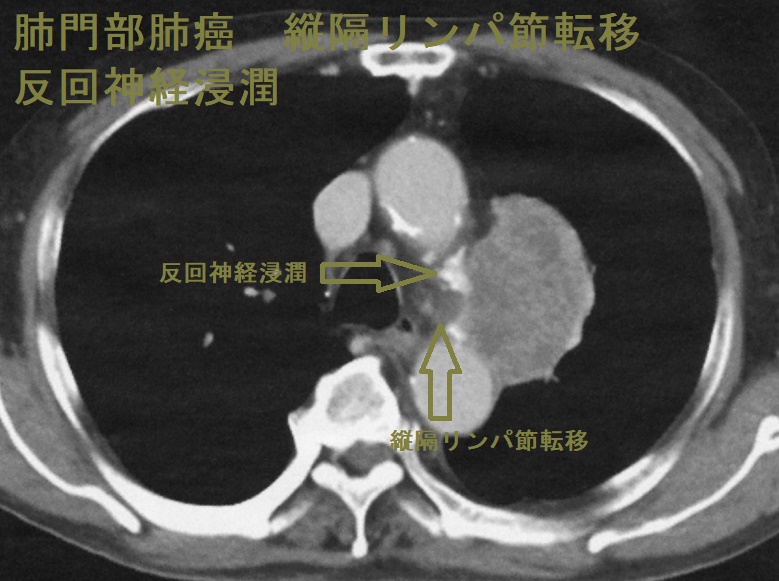

肺門部肺癌 縦隔リンパ節転移 反回神経浸潤

肺門部肺癌(中心型肺癌) 縦隔リンパ節転移 反回神経浸潤

肺門部肺癌(扁平上皮癌が多い)は、発熱や咳嗽(せき)がなく血痰のみで、胸部単純CTをしても異常を認めない場合があります。喀痰細胞診の検出感度は約40% にすぎないが、パパニコロウ(Papanicolaou)染色でオレンジGに染まる細胞があれば扁平上皮癌です。